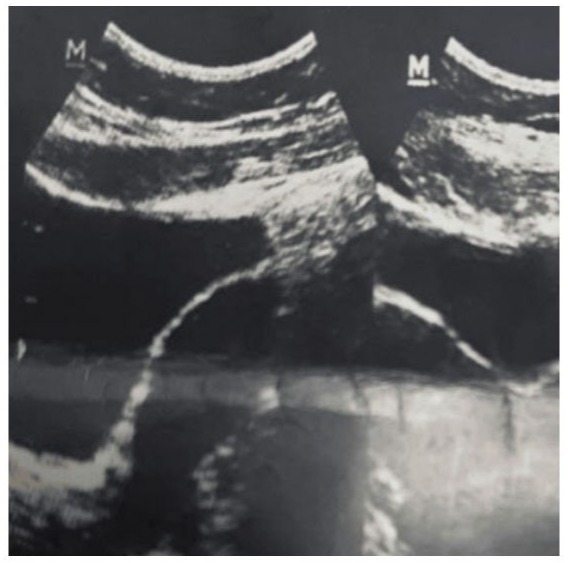

On admission, the patient was hemodynamically stable. A transvaginal scan revealed probe tenderness and identified a mixed echogenic mass measuring 5x7.2 cm, with an elongated appearance in contact with two uterine cavities.

Figure 1: High resolution transvaginal ultrasound image showing a mixed ecorefringence mass which could correspond with and endometrioma vs. hematometrocolpos